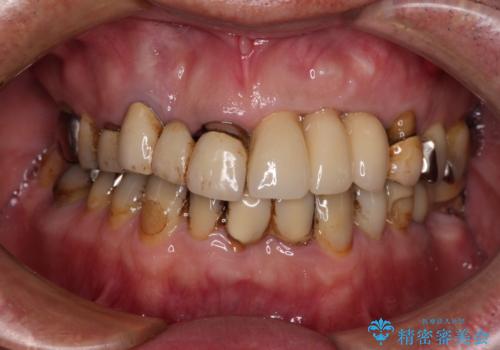

転倒で折れてしまった前歯 インプラントによるオールセラミックブリッジ治療

- 転倒により前歯3本が折れてしまったとのことで、インプラントによる治療を希望して来院された患者様です。

既に近医で真ん中の歯1本は抜歯されており、その隣の2本も破折していると言われたとのことでした。

診断をした結果、前医の診断の通り、2本とも破折しており、既に抜去している歯を含めて3本の抜歯が必要な状態でした。

抜歯する歯の両隣も治療が必要と思える歯であったため、広範囲なオールセラミックブリッジによる治療も提案しましたが、患者様本人の希望もあってインプラント2本による欠損部のみのブリッジ治療を行うこととしました。